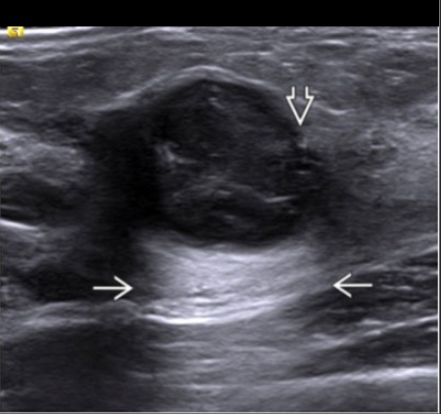

Ultrasound shows an oval heterogeneous hypoechoic mass with overall indistinct margins (though portions are circumscribed) and posterior acoustic enhancement

Invasive tumors with increased through transmission (i.e., posterior acoustic enhancement) are 10-24x more likely to be high grade than invasive tumors without this feature.

The exact cause of this feature remains unclear; however, theories propose that it may be related to the high cellular content, organization of the tumor cells, &/or lack of a desmoplastic reaction (due to its rapid growth). Invasive lobular carcinomas are usually well differentiated (grade 1) in general and usually associated with posterior shadowing.